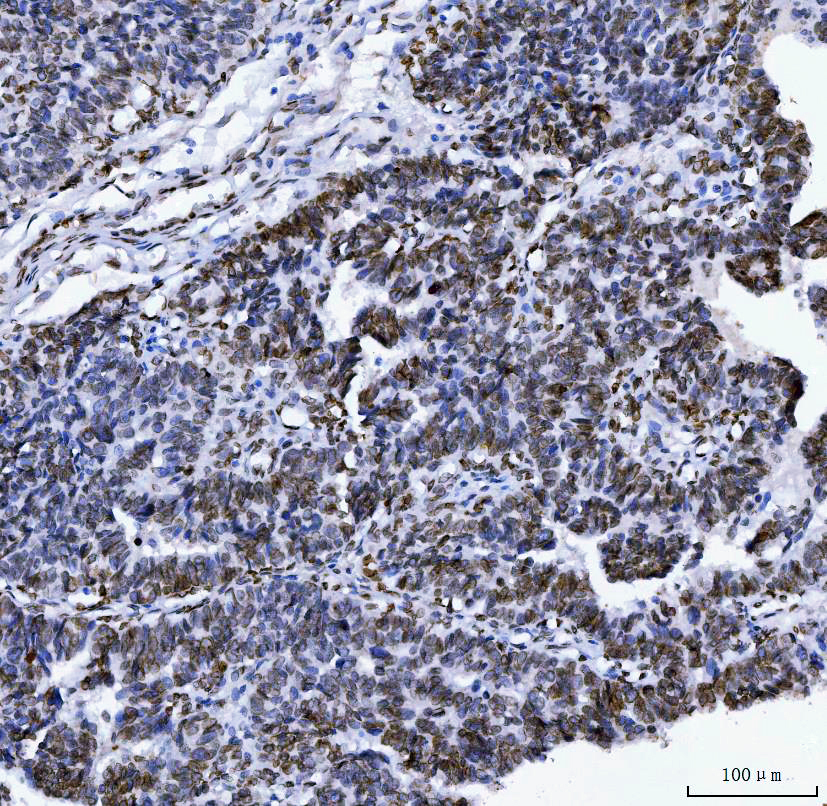

IHC analysis of Lamin A/C using anti-Lamin A/C antibody (M00438-6).

Lamin A/C was detected in a paraffin-embedded section of human ovarian cancer tissue. The tissue section was incubated with mouse anti-Lamin A/C Antibody (M00438-6) at a dilution of 1:200 and developed using HRP Conjugated mouse IgG Super Vision Assay Kit (Catalog # SV0001) with DAB (Catalog # AR1027) as the chromogen.